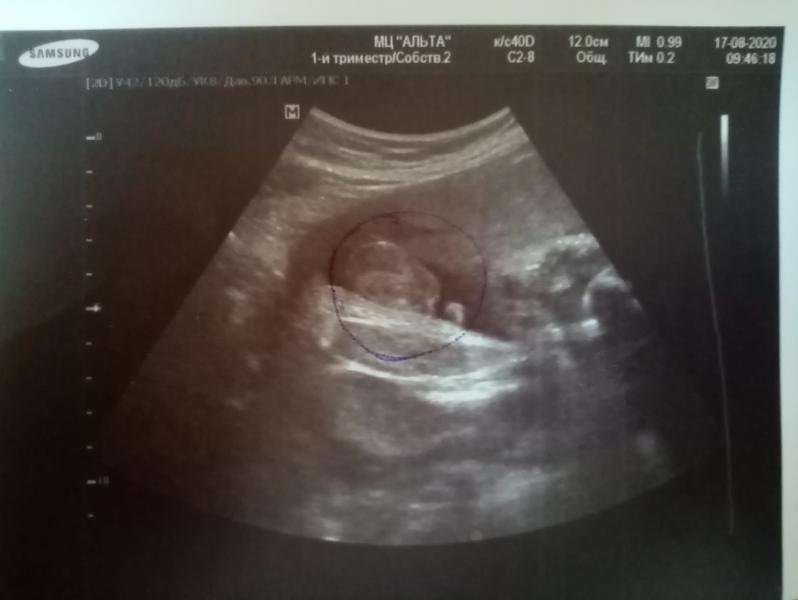

Съездила сегодня в медцентр Альта на третий скрининг и доплерографию. Сыночек мой весит 2 кг, развивается хорошо🤗. Это самое главное 🙏🙏🙏. Не понравилось одно, что не прошло и 5 минут она говорит всё можете вставать. Я то думала доплерографию делают минимум 30 минут